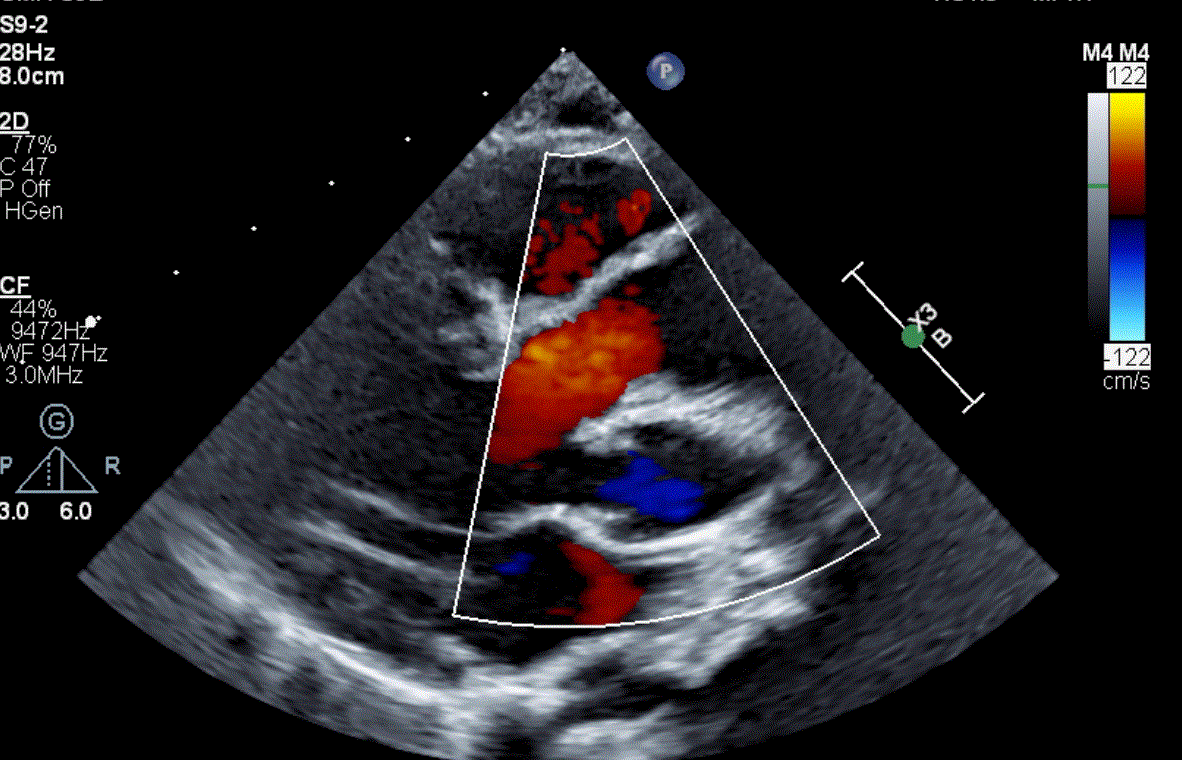

What congenital defect is shown here?

What is Absent Pulmonary Valve